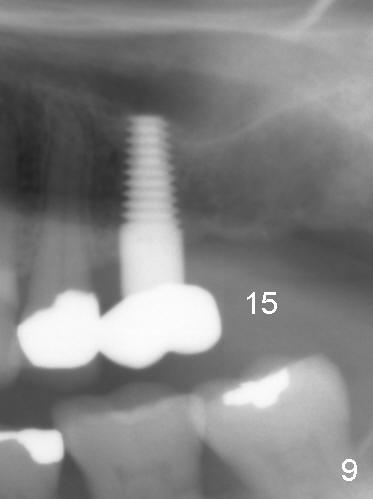

One year 2 months post cementation, the patient complains of inability to chew on the left. It appears that the crown at the site of #14 (Fig.8) is not as large as the tooth #3 (Fig.7); the occlusal contact of the crown is less than that of the tooth #3. The complaint remains the same after crown being remade. It appears that implant at #15 is needed (Fig.9: 1 year 9 months post cementation of #14 crown). The crestal cortical bone is thicker around the implant 2 years 4 months post cementation (Fig.10).